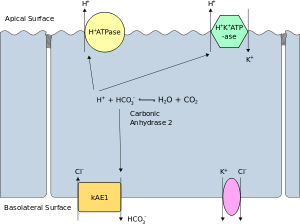

Distal renal tubular acidosis (dRTA) or Type 1 renal tubular acidosis (RTA) is the classical form of RTA, being the first described. Distal RTA is characterized by a failure of acid secretion by the alpha intercalated cells of the cortical collecting duct of the distal nephron. This failure of acid secretion may be due to a number of causes, and it leads to an inability to acidify the urine to a pH of less than 5.3.

- Hereditary causes include mutations of Band 3[9] the basolateral bicarbonate transporter of the intercalated cell, which may be transmitted in an autosomal dominant fashion in western European cases, or in an autosomal recessive fashion in South East Asian cases. The South East Asian cases are associated with more severe hypokalemia.[10] Other hereditary causes include mutations of subunits of the apical proton pump vH+-ATPase,[11] which are transmitted in an autosomal recessive fashion, and may be associated with sensorineural deafness.[12]